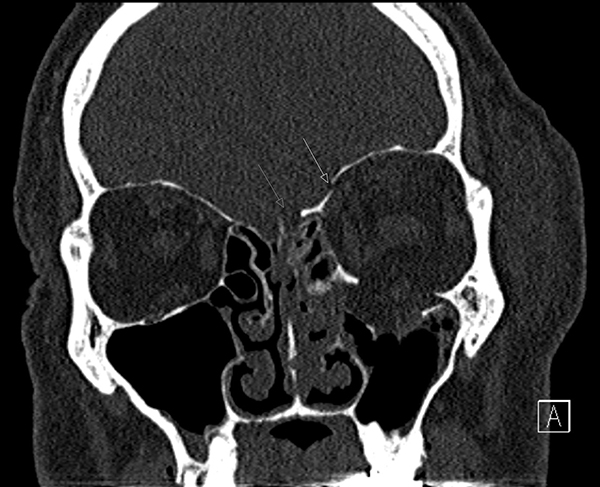

Fallbeskrivning Första svenska beskrivningen av läckage av cerebrospinalvätska kranioorbitalt